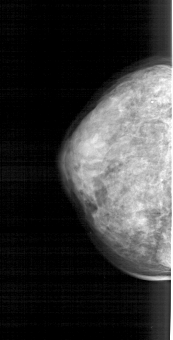

A_1660_1.RIGHT_MLO

RIGHT_CC LINES 5041 PIXELS_PER_LINE 1921 BITS_PER_PIXEL 12 RESOLUTION 43.5 OVERLAY

FILE: A_1660_1.RIGHT_CC.OVERLAY

TOTAL_ABNORMALITIES 1

ABNORMALITY 1

LESION_TYPE CALCIFICATION TYPE PUNCTATE DISTRIBUTION SEGMENTAL

ASSESSMENT 4

SUBTLETY 1

PATHOLOGY BENIGN

TOTAL_OUTLINES 1

BOUNDARY